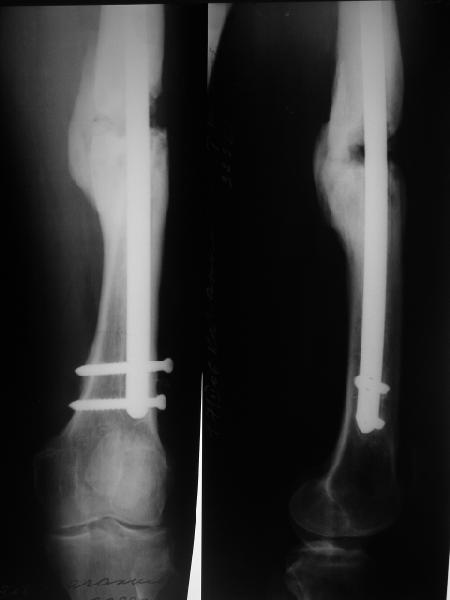

Возможно, проф. Лазарев предложит другой вариант, а в наших условиях мы бы закрыто заштифтовали бы бедро антеградно. Устранили бы варус, используя голень как рычаг, вероятнее всего, даже дистрактор не понадобился бы. В приницпе, можно и ретроградно ири наличии движений в колене, но варус будет труднее устранить - можно и предварительно аппаратом в таком случае.

Стержень можно использовать и обычный потолще, но лучше бы с возможностью введения большего, чем два фронтальных, числа запирающих винтов.

Учитывая наличие этой мощной спайки, запереть можно сразу динамически.

Рефрактур уж точно можно будет не опасаться, а за несколько месяцев даже при отсутствии заполнения костью по всей окружности, этот обходной "мостик" упрочнится и возьмет на себя нагрузку. В приложении пример такого рода "эндопротезирования диафиза", прошло больше 3 лет.

Пациентка, страдающая еще и инсулинозависимым диабетом, не хромает, работает инженером.